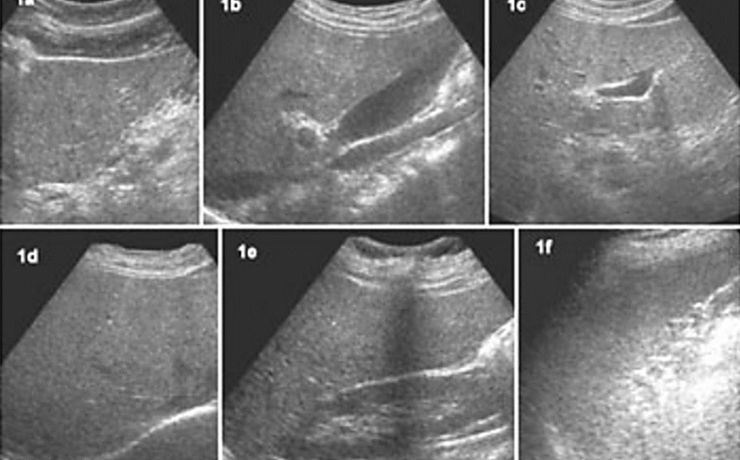

La vesícula biliar es una bolsa de 7 a 10cm de longitud y de 3 a 5 cm de ancho, la cual mantiene en promedio un volumen de 30-50ml; tiene forma piriforme (forma de pera), la cual se divide para su estudio en tres secciones: el fondo, el cuerpo y